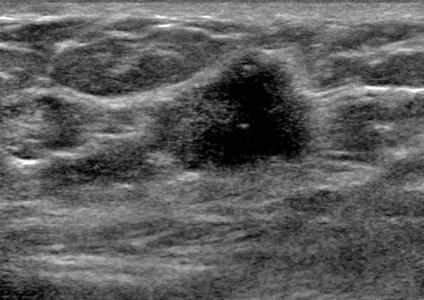

The target dataset was developed from 35 breast ultrasound scans that were segmented by an image-processing expert with extensive experience in breast lesion segmentation (the second author). The images, collected from the Web, are of different dimensions, ranging from to pixels (Figure 3, images resized for sake of illustration). These are the same images used to introduce EFIS originally [1].

Ultrasound images are generally difficult to segment, primarily due to the presence of speckle noise and low level of local contrast. It should be noted that the segmentation of ultrasound actually does require a complete processing chain, (including proper preprocessing and post-processing steps). However, the purpose of using these images was solely to demonstrate that the accuracy of the segmentation can be increased with the application of SC-EFIS.